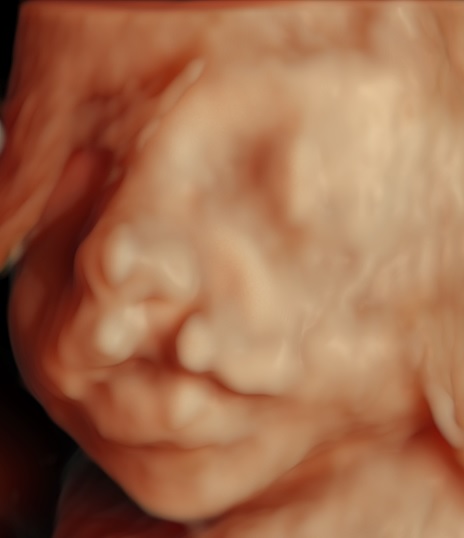

Casus1

Casus2

Casus3

Casus4

Casus5